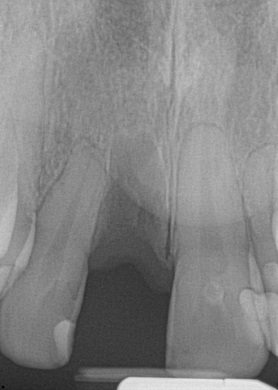

Fig 16. Preoperative periapical radiograph on the day of surgery.

Figure 16

A 23-year-old man reported to the dental practice on January 3. Apparently, while on vacation and celebrating the New Year, the patient experienced a loss of equilibrium and found himself horizontal in the crosswalk. When surveying the damages, his friends noticed he was missing tooth No. 8. Those who were involved were not able to find the missing maxillary central incisor. The young man was eventually seen about 3 days after the trauma. A CBCT radiograph, study models, and photographs were collected, and teeth Nos. 6 through 10 were immobilized with composite and 20 x 20 orthodontic wire (Figure 14). The CBCT and photos were emailed to the dental laboratory, and the analog intraoral impression with a centric occlusion bite registration was sent via ground transportation. Due to the nature of the trauma, the laboratory and the author expeditiously converted the analog diagnostics and merged all the patient's data sets to develop the plan. Based on the 3D data sets, the laboratory and the dentist were able to accurately assess the volume of bone and soft tissue remaining after the trauma. The volume was still intact and soft tissue was plentiful (Figure 15 and Figure 16).

The decision was to develop a surgical guide, place the implant, and fabricate a screw-retained one-piece non-engaging abutment with a slender emergence profile and a polymethyl methacrylate (PMMA) provisional. Ten days after the trauma, the patient was seen in the dental office for the placement of the dental implant. On the day of surgery, a 3D-printed surgical guide was used, developed from the CBCT radiograph and the digitized impressions (Figure 17 and Figure 18).